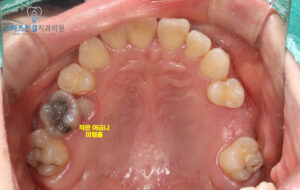

인접한 작은 어금니가

잇몸 속에 묻혀 있는

미맹출 상태였기 때문이에요.

해당 치아는 위치상 교정을 통해

살려보는 방법도 검토했지만,

뿌리가 짧고 전반적인 예후가

좋지 않다고 판단되었어요.

이에 화서동치과 스마트한결은

장기적인 안정성과

향후 재치료 가능성을 고려해,

큰 어금니와 함께 발치를

진행하기로 결정했답니다!